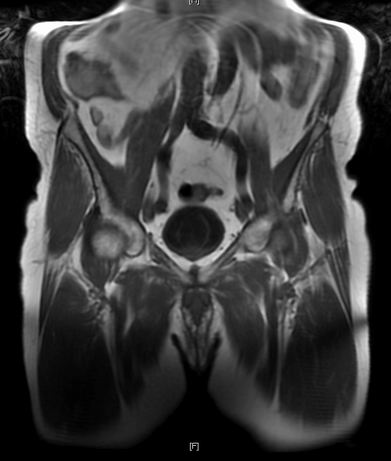

The good news was not to last. On 9/1/23 my PSA was unexpectantly high, suggesting a nasty strong decrease in doubling time. My consultant sent me to have another Computer Tomography X-ray scan and this time the results were not so good. I had a slight increase in the size of two pelvic lympth glands. On the screen they looked small enough but my consultant was worried: it could be the start of matastatis. He wanted further information from Positron Emission Tomography, with the possibility of further radiatherapy if these results were satisfactory.

On 25/5/23 on a lovely sunny morning I cycled to the Churchill for the PET scan. They give you a radioactive injection and ask you to isolate from others for a half hour before the scan. Unlike MRI, PET scans are quite quiet and took around 20 minutes. The result shown on the right shows my prostate with the big red signal and the little red and yellow dot North-East is my metastatic pelvic lympth node. The strong signal from the prostate meant the a second radiotherapy was not an option. I had "advanced" metastatic prostate cancer.